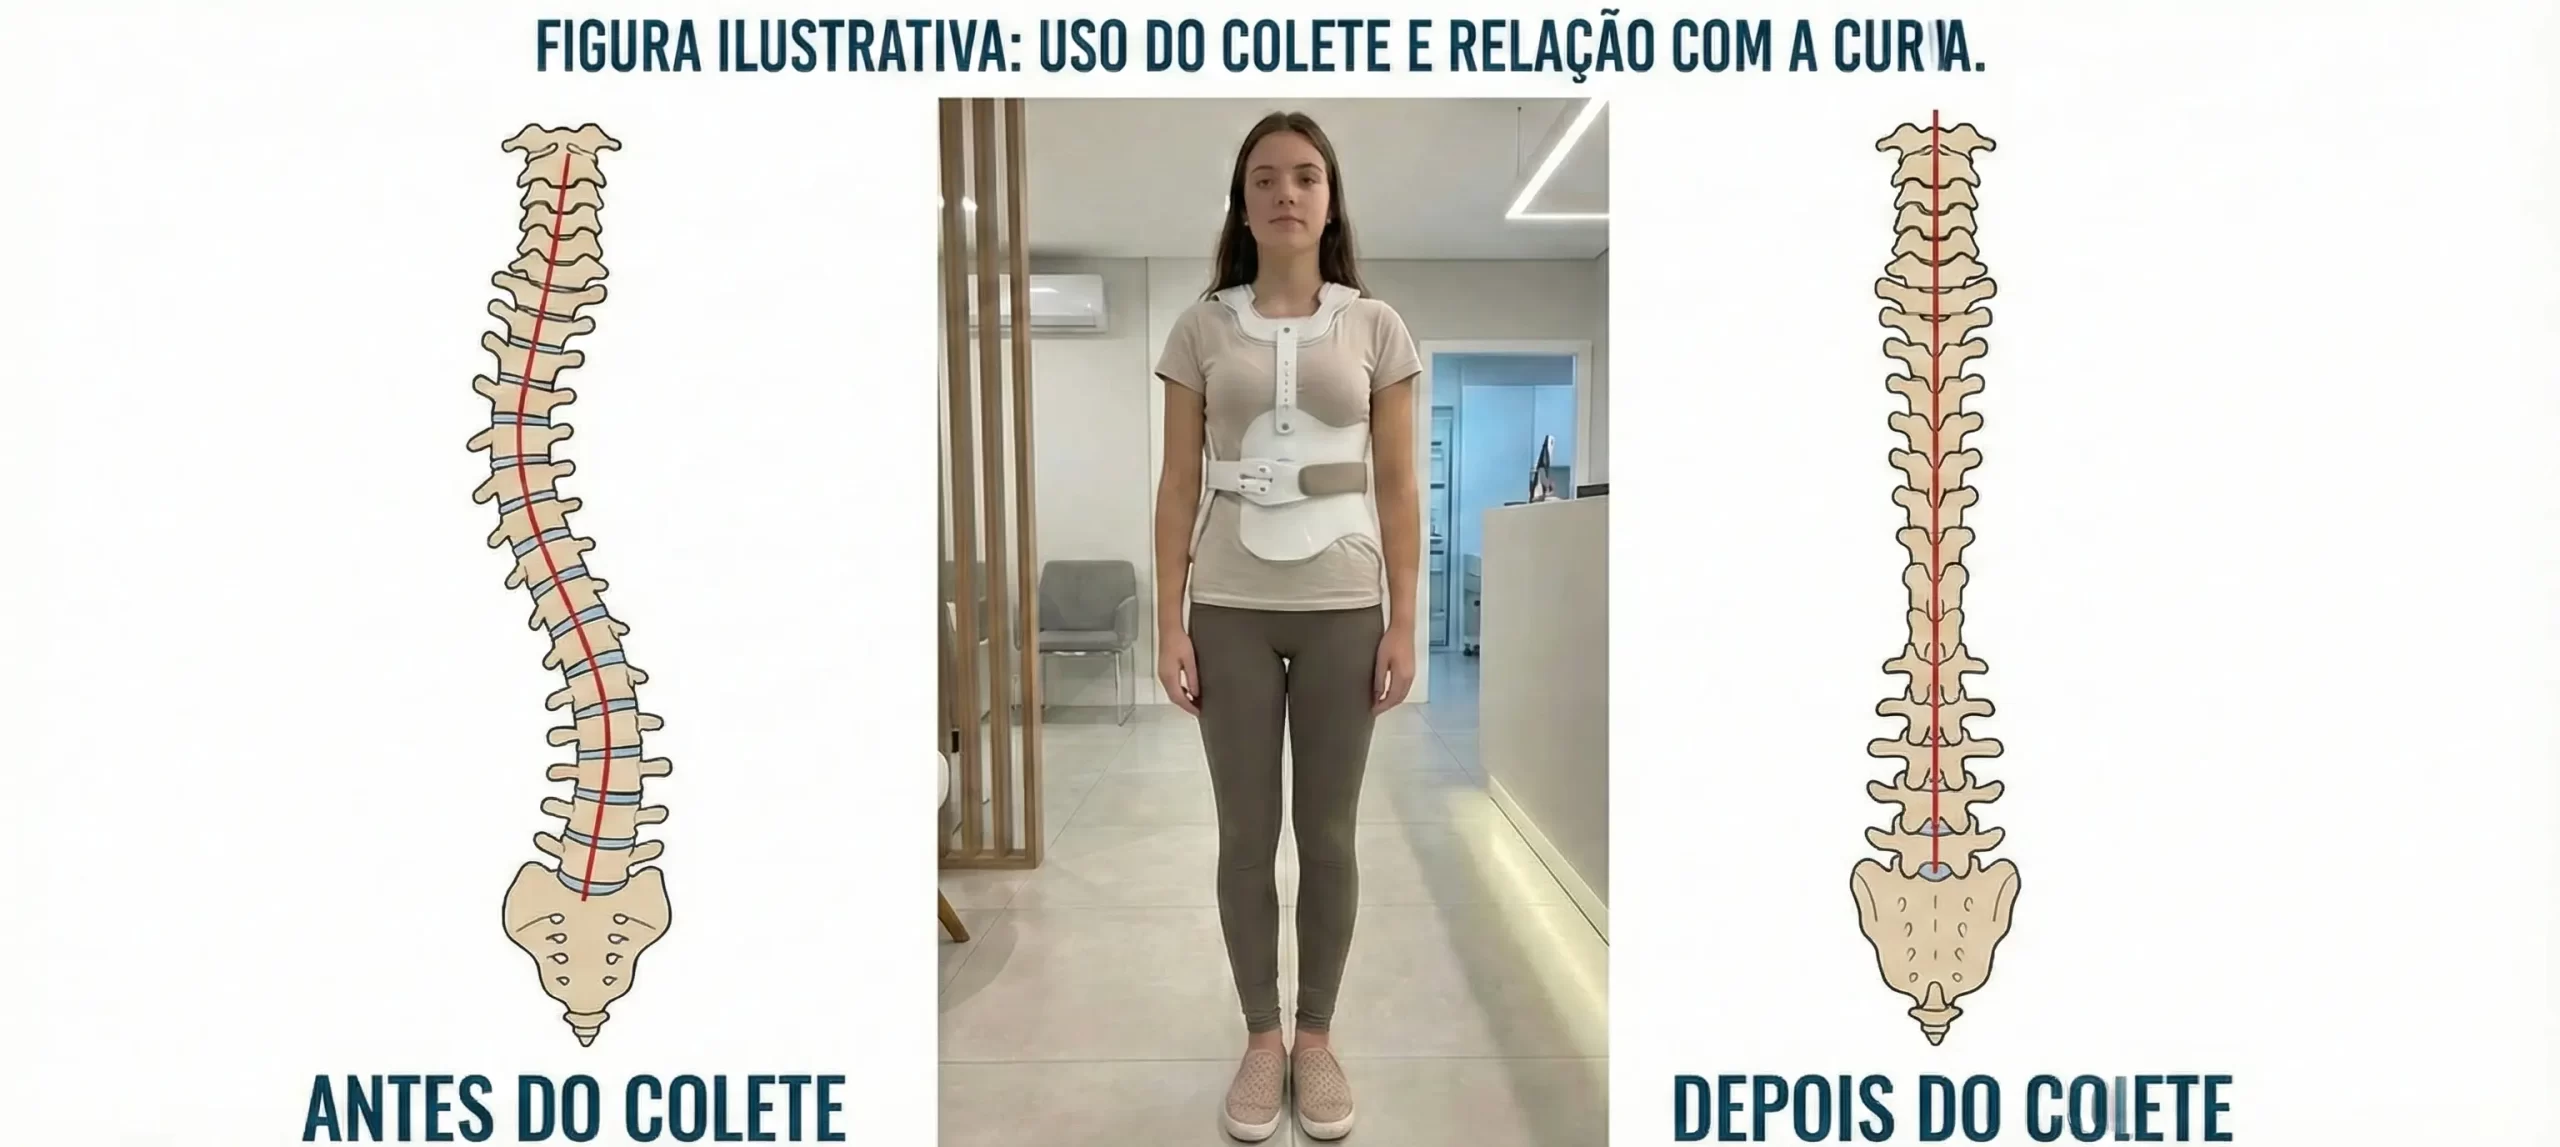

O colete para escoliose é um dispositivo ortopédico utilizado para impedir a progressão da curva escoliótica em crianças e adolescentes que ainda estão em fase de crescimento.Ele não tem como objetivo “desentortar” completamente a coluna, mas sim evitar que a curva piore até que o paciente complete o crescimento ósseo.Exemplo visual de colete e alinhamento

Comparativo antes/depois